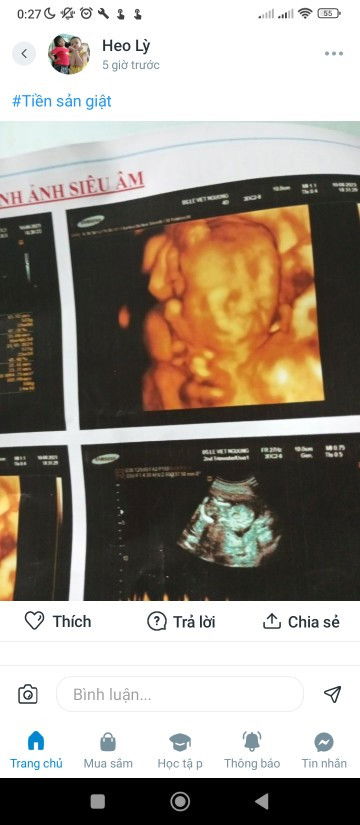

Em đi siêu âm được,16tuan hình ảnh siêu âm giống hở hàm ếch quá.e lo ghe luôn.hoi bs thì bs bảo 3tuan nữa siêu âm lại mới biết được.

Hình ảnh nhiều khi khó nhìn đó m ah